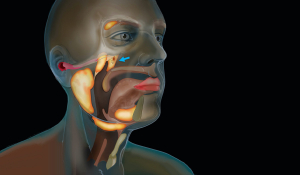

Видалення слинних залоз

Слинні залози у нашому організмі відповідальні за вироблення слини – рідини, яка важлива для травлення та очищення порожнини рота, захисту зубів від мікроорганізмів. Однак у них можливі запальні процеси, утворення різного ступеня інтенсивності та вираженості.